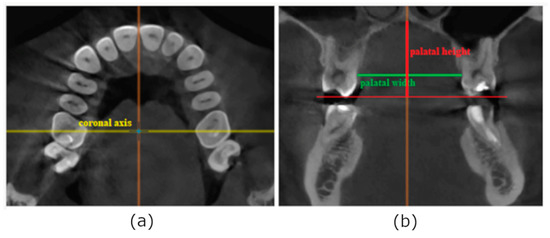

IZC bone thickness was measured at the level of the mesiobuccal and distobuccal root of the first permanent molar and between the first and second molar as presented in the Figure 1. To localize the buccal roots of the first molar, a horizontal view was used. In the sagittal view, the horizontal axis was located at the level of ½ height of the roots. Subsequently, a picture of the maxilla in horizontal projection was rotated in relation to the coronal axis to obtain an angle of 90° between the coronal axis and buccal surface of the alveolar process at the level of point M (mesial buccal root of the first molar), point D (distal buccal root of the first molar), and point I (interdental space between the first and the second molar) to imitate clinical conditions during mini-implant placement. Using the occlusal plane as a reference line, three points in the vertical plane were defined in modified coronal view at the levels of 12 mm, 14 mm, and 16 mm from the occlusal plane as points of potential mini-implants insertion. All the measurements were taken at an angle of 70 degrees to the occlusal plane, on the patients’ left side.

Figure 1. Measurement of bone depth on CBCT scans: (a)—sagittal slice consisting of mesiobuccal root of the first permanent molar used to obtain horizontal slice; (b)—horizontal view of the maxilla rotated in relation to the coronal axis to obtain a cross-section of the alveolar process at the level of M1; (c)—measurement of IZC thickness in modified coronal view.